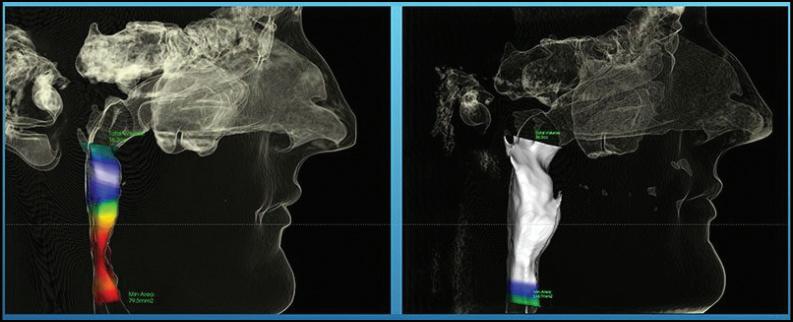

Contrary to conventional belief, pediatric dentists with specialized training are well-equipped to address symptoms related to sleep and airway conditions. The airway, mode of breathing, and malocclusion are closely interconnected and should be addressed early and holistically by dentists. Advanced technology, such as cone beam 3D imaging, allows dentists to effectively diagnose airway issues and guide proper growth and development. Early intervention is essential in guiding proper growth and development.

Convenient at-home sleep study tests are now available to diagnose pediatric sleep apnea and breathing issues. These tests provide comprehensive, accurate data for proper diagnoses.

Treatment goals encompass the elimination of detrimental habits, guiding optimal cranial, jaw, and facial development, preventing dental misalignment, and enhancing airway health and oxygen sufficiency. Various therapies, including oral appliances, myofunctional therapy and positive airway pressure therapy, can effectively alleviate symptoms.